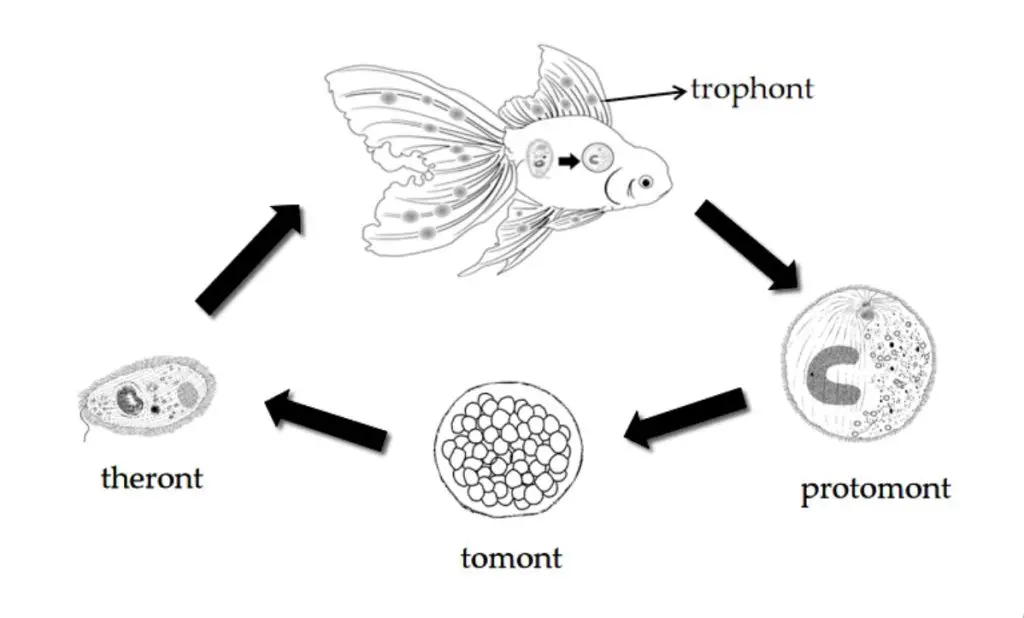

چرخه زندگی انگل ایکتیوفتیریوس مولتیفیلیس شامل سه مرحله هست: تروفونت (انگلی)، تومونت (تولیدمثلی) و ترونت (عفونت زا).

این انگل چرخه زندگی مستقیم و بدون میزبان واسط داره و یه انگل اجباری محسوب میشه یعنی برای زنده موندنش حتما به ماهی نیاز داره و اگه ماهی تو سیستم نباشه این انگل میمیره.

سیکل زندگی این انگل شامل یک مرحله عفونت زا به نام ترونت (Theront ) و یک فرم فعال و آسیب رسان به نام تروفونت (Trophont ) میباشد، که منجر به عفونت انگلی روی بدن ماهی میشه. به عبارت بهتر اول از همه ترونت های متحرک (مرحله اول زندگی انگل ایک) که توی آب در حال شنا کردن هستن خودشون رو به ماهی میرسونن و به بافت سطحی پوست، آبشش ها، باله ها و سایر سطوح بدن ماهی حمله میکنن و به دورن اونها نفوذ میکنن.

بعد از اون این ترونتها در بافت ماهی بالغ میشن و تبدیل میشن به تروفونت. به همین خاطره که به مرحله اول زندگی انگل ایک یا همون ترونت میگن عفونت زا چون شروع بیماری با اونه ولی به مرحله دوم که تروفونت هست میگن مرحله انگلی چون در واقع مرحله تروفونت هست که از ماهی تغذیه میکنه و به ماهی آسیب میزنه.

تروفونت انگل به شکل دونه های سفید کوچک در سطح بدن ماهی دیده میشه و ظاهری شبیه به گرد نمک ایجاد میکنن. تروفونت ها تو اپیتلیوم بافت های مخاطی ماهی مستقر میشن و از اونجا تغذیه میکنن و از 30 الی 40 میکرومتر تا 1000 میکرومتر در طی هفت روز در دمای 20 درجه سانتیگراد رشد میکنن.

بعد از اینکه مرحله دوم زندگی انگل ایک کامل شد، انگل به شکل پروتومونت (Protomont) از ماهی خارج میشه (پروتومونت جز مراحل اصلی زندی ایک نیست و مابین مرحله دوم و سوم قرار میگیره، درواقع انگلیه که داره از مرحله دوم به سوم تبدیل میشه). بعد از اون انگل یک کیست پروتئینی شفاف را روی بستر محیطی موجود ایجاد میکنه که بهش میگن تومونت. در داخل تومونت فرم عفونتزای انگل یا همون ترونت ایجاد میشه که متعاقباً ترونت، کیست رو سوراخ میکنه و به بیرون از کیست شنا میکنه و دوباره خودش رو به یه ماهی دیگه میرسونه و این چرخه سه مرحله ای دوباره تکرار میشه.

طول چرخه زندگی انگل به دمای آب بستگی دارد. چرخه زندگی انگل در دمای 25 درجه سانتیگراد طی سه تا شش روز، در دمای 15 درجه سانتی گراد در 10 روز و در دمای 10 درجه سانتیگراد تو مدت زمان یک ماه یا بیشتر کامل میشه.

از اونجایی که تروفونت های این انگل (مرحله دوم که روی بدن ماهیه) در عمق پوست نفوذ میکنن و خودشون رو از اثر داروهایی که به طور معمول برای درمان انگل های پوستی استفاده میشن حفظ می کنن، بهترین زمان مبارزه با انگل مرحله ایه که انگل روی بدن ماهی نیست و داره در آب شنا میکنه؛ پس داروها فقط روی فرم آزاد انگل که همون ترونت (مرحله اول) میشه موثر هستن و درمان باید طولانی مدت باشه و چندین بار با فاصله های مختلف (با توجه به دمای آب) تکرار بشه و حمام های کوتاه مدت خیلی روی این انگل کارساز نیست.

بنابراین ترونت ها حساس ترین مرحله زندگی انگل به درمان هستن که برای درمان، ماهی باید به میزانی در معرض ترکیبات درمانی قرار بگیره که انگل ایک مرحله دوم و سوم رو سپری کنه و وارد مرحله یک بشه. بدین ترتیب، حذف یک مرحله از زندگی انگل موجب قطع چرخه زندگی اون شده که یکی از اهداف درمانه.